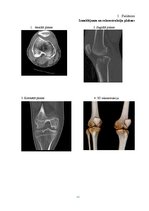

1.2.  Ceļa locītavas datortomogrāfijas anatomija    15

3.  CEĻA LOCĪTAVAS DATORTOMOGRĀFIJA    24

3.2.  Ceļa locītavas DT izmeklēšanas    25

3.3.  Ceļa locītavas izmeklējuma kvalitātes kritēriji    28